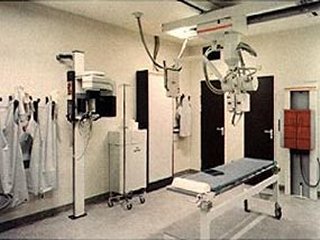

quirofano (1) |

quirofano- (1) |

| quirofano (1) |

quirofano- (2) |

quirofano (2) |

| quirofano- (3) |

quirofano (3) |

quirofano (4) |

| quirofano (5) |

quirofano (6) |

quirofano |

| quirofano- |

quirofano |